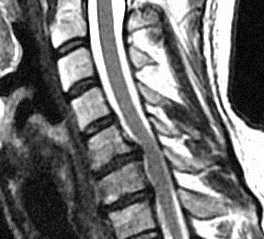

МРТ шейного отдела позвоночника. Стеноз позвоночного канала . Сагиттальная Т2-взвешенная МРТ.

Комплекс дегенеративных изменений позвоночника может приводить к сужению позвоночного канала и/или бокового кармана, видимое при КТ и МРТ позвоночника. Часто это состояние обозначают термином “спондилёз”. Этому способствует также врождённая узость канала вследствие коротких корней дуг.